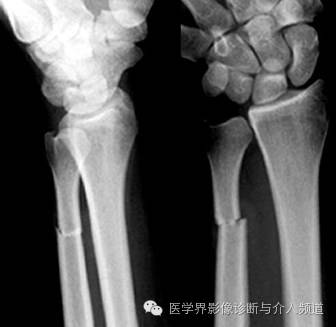

14、Galeazzi 骨折

桡骨中段骨折并下桡尺关节脱位。摔倒时用手撑地或直接暴力打击腕关节背侧造成。

15、Essex Lopresti 骨折:

桡骨小头粉碎性骨折,伴下桡尺关节脱位。多有高处坠下造成。